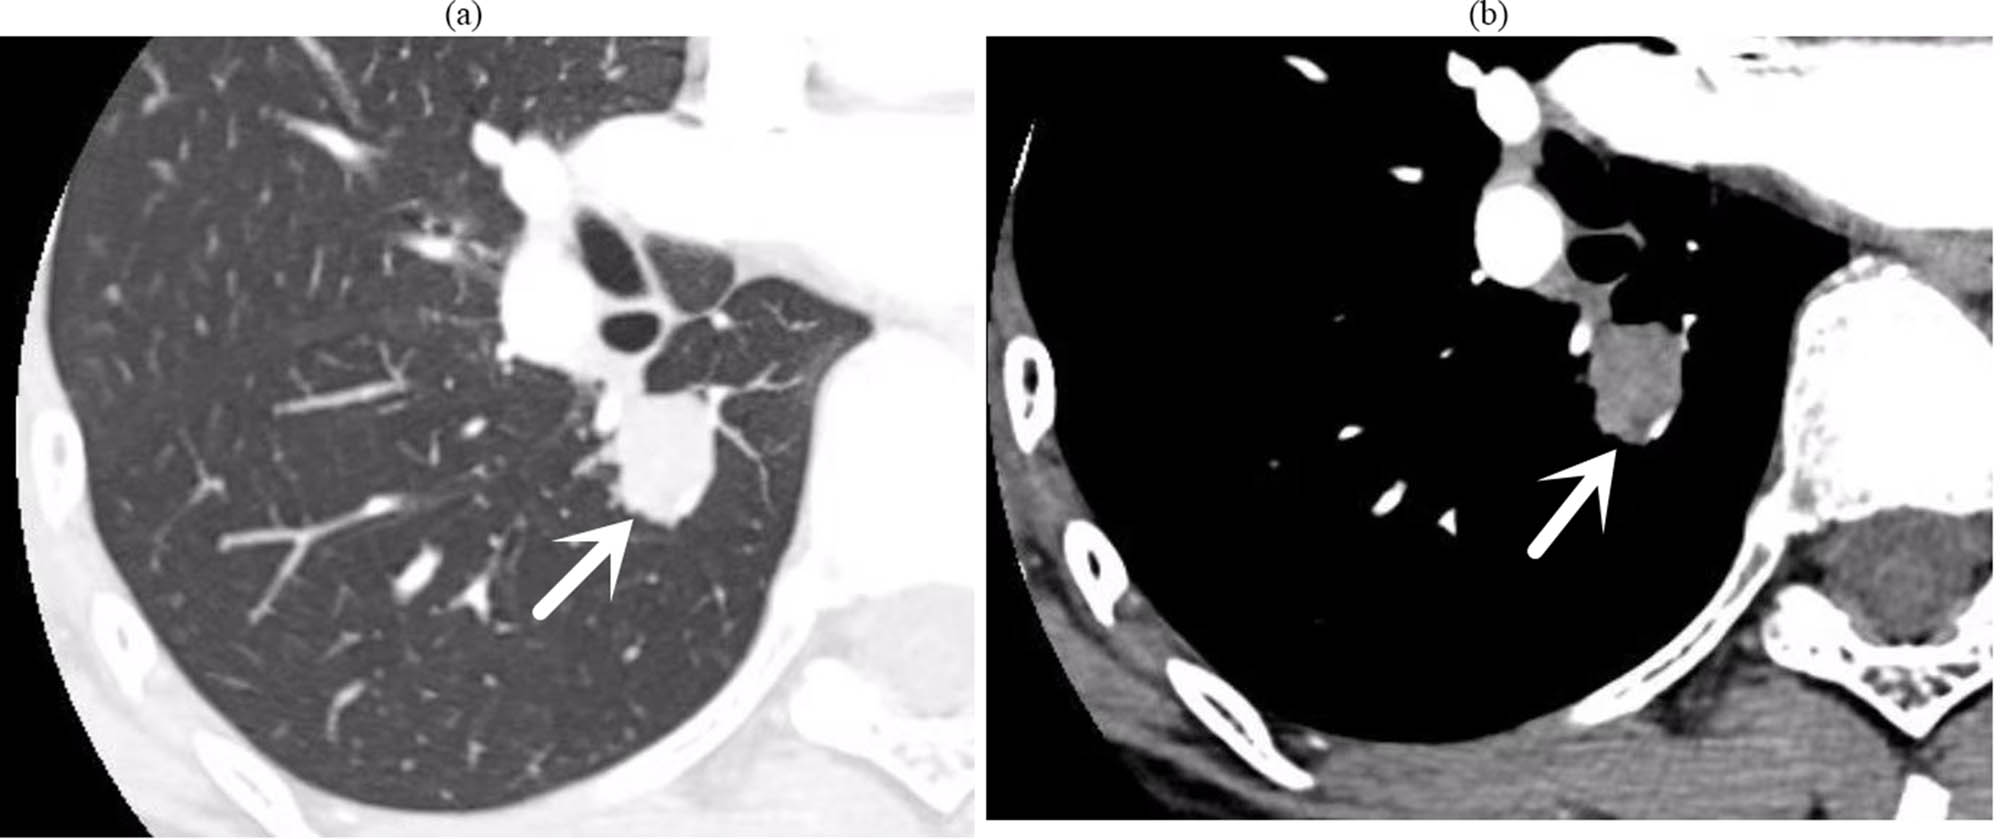

Upon admission, sputum smears revealed no acid-fast bacilli. Lung tumour marker screenings (CEA, CA125, CA-125, and CYFRA21-1) were unremarkable, and routine laboratory tests did not reveal any notable abnormalities. A low-dose CT scan of the chest with targeted enhancement on 26 September 2023 identified nodular shadows in the right lower lobe (Figure 2), raising suspicion of a tumour. Bronchoscopic biopsy or thoracic surgery was advised. Additionally, multiple ground-glass opacities were observed in both lungs, which may indicate hyperplastic or chronic inflammatory lesions, necessitating further monitoring. Linear opacities in both lungs and potential chronic inflammation were noted, with re-examinations scheduled. An abdominal CT on 27 September 2023 detected calcified lesions in the liver. Cardiac ultrasound revealed no notable structural or flow abnormalities. Ultrasound of superficial lymph nodes (neck, axilla, and groin) revealed no pathological changes. Venous ultrasound of the lower extremities was also normal, with no issues detected in deep or superficial veins. Brain magnetic resonance imaging (both plain and enhanced scans) revealed no significant lesions. Bronchoscopy on 28 September 2023 identified a smooth, pedunculated mass obstructing the airway in the dorsal segment of the right lower lobe, which moved slightly with respiration and was prone to bleeding upon contact. A biopsy was deferred to minimise the risk of bleeding (Figure 3). The ECT scan on 29 September 2023 revealed the following: (1) increased metabolic activity in the left first anterior rib, suggesting the need for follow-up in 3–6 months; (2) increased metabolic activity in both knee joints, consistent with degenerative changes; (3) similar changes in the cervical spine; and (4) no notable abnormalities in other skeletal regions, although further imaging may be considered as needed.

(a) (Lung window), (b) (mediastinal window) chest target-enhanced CT: small nodules in the dorsal segment of the right lower lobe, with punctate calcifications visible within it, surrounded by multiple punctate and nodular shadows; nodular growth was seen in the dorsal segment of the bronchus.